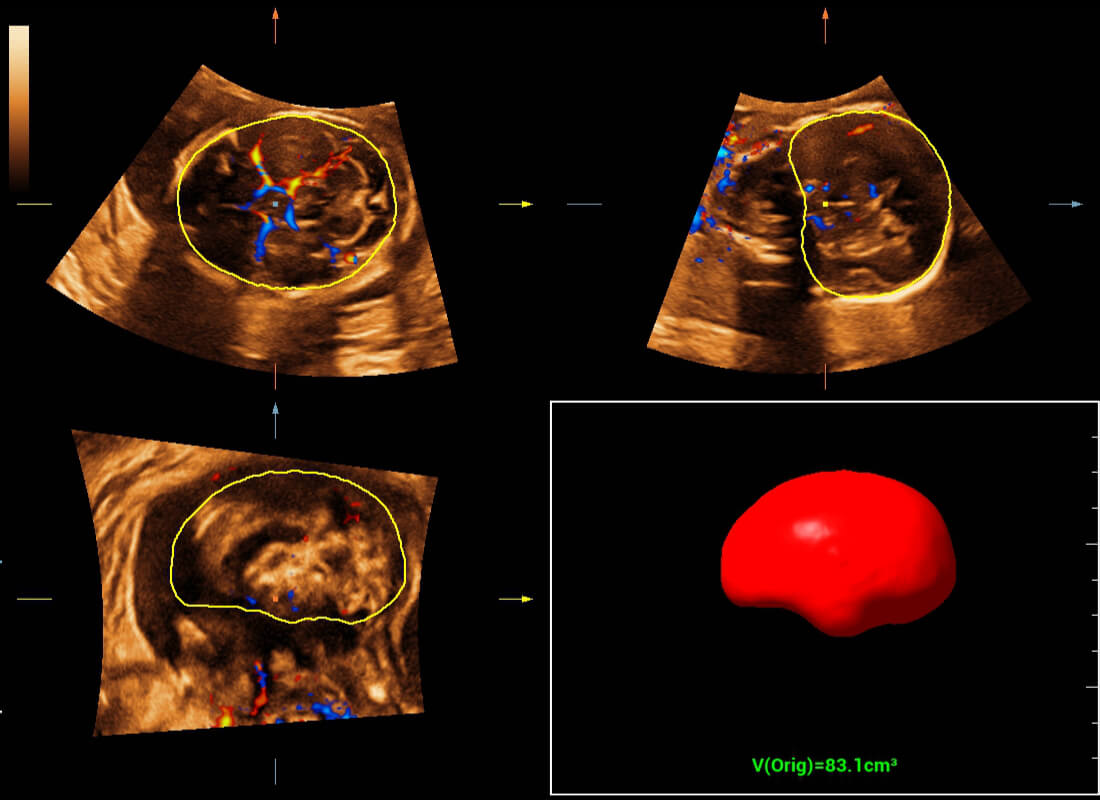

Central nervous system (CNS) malformations are one of the most common congenital abnormalities. Unfortunately, due to imaging limitations such as poor fetal position, acoustic shadowing, and operatorsŌĆÖ poor scanning skills, the MSP is particularly difficult to find in a 2D ultrasound. In this case, a faster and more user-friendly method, which automatically displays the standard planes together with the required measurements in a fetal CNS examination, could significantly boost both the quality and efficiency of clinical diagnoses.?NuewaŌĆÖs intelligent solution of fetal brain can realize automatic acquisition of brain volume data based on intelligent recognition of CNS application scenarios, intelligent generation of four fetal brain standard planes including MSP, automatic measurement of CNS biological items and automatic evaluation of fetal brain volume. More importantly, Nuewa's leading color Doppler technology can provide a clear and sensitive dynamic display of blood flow in the tiny vessels.